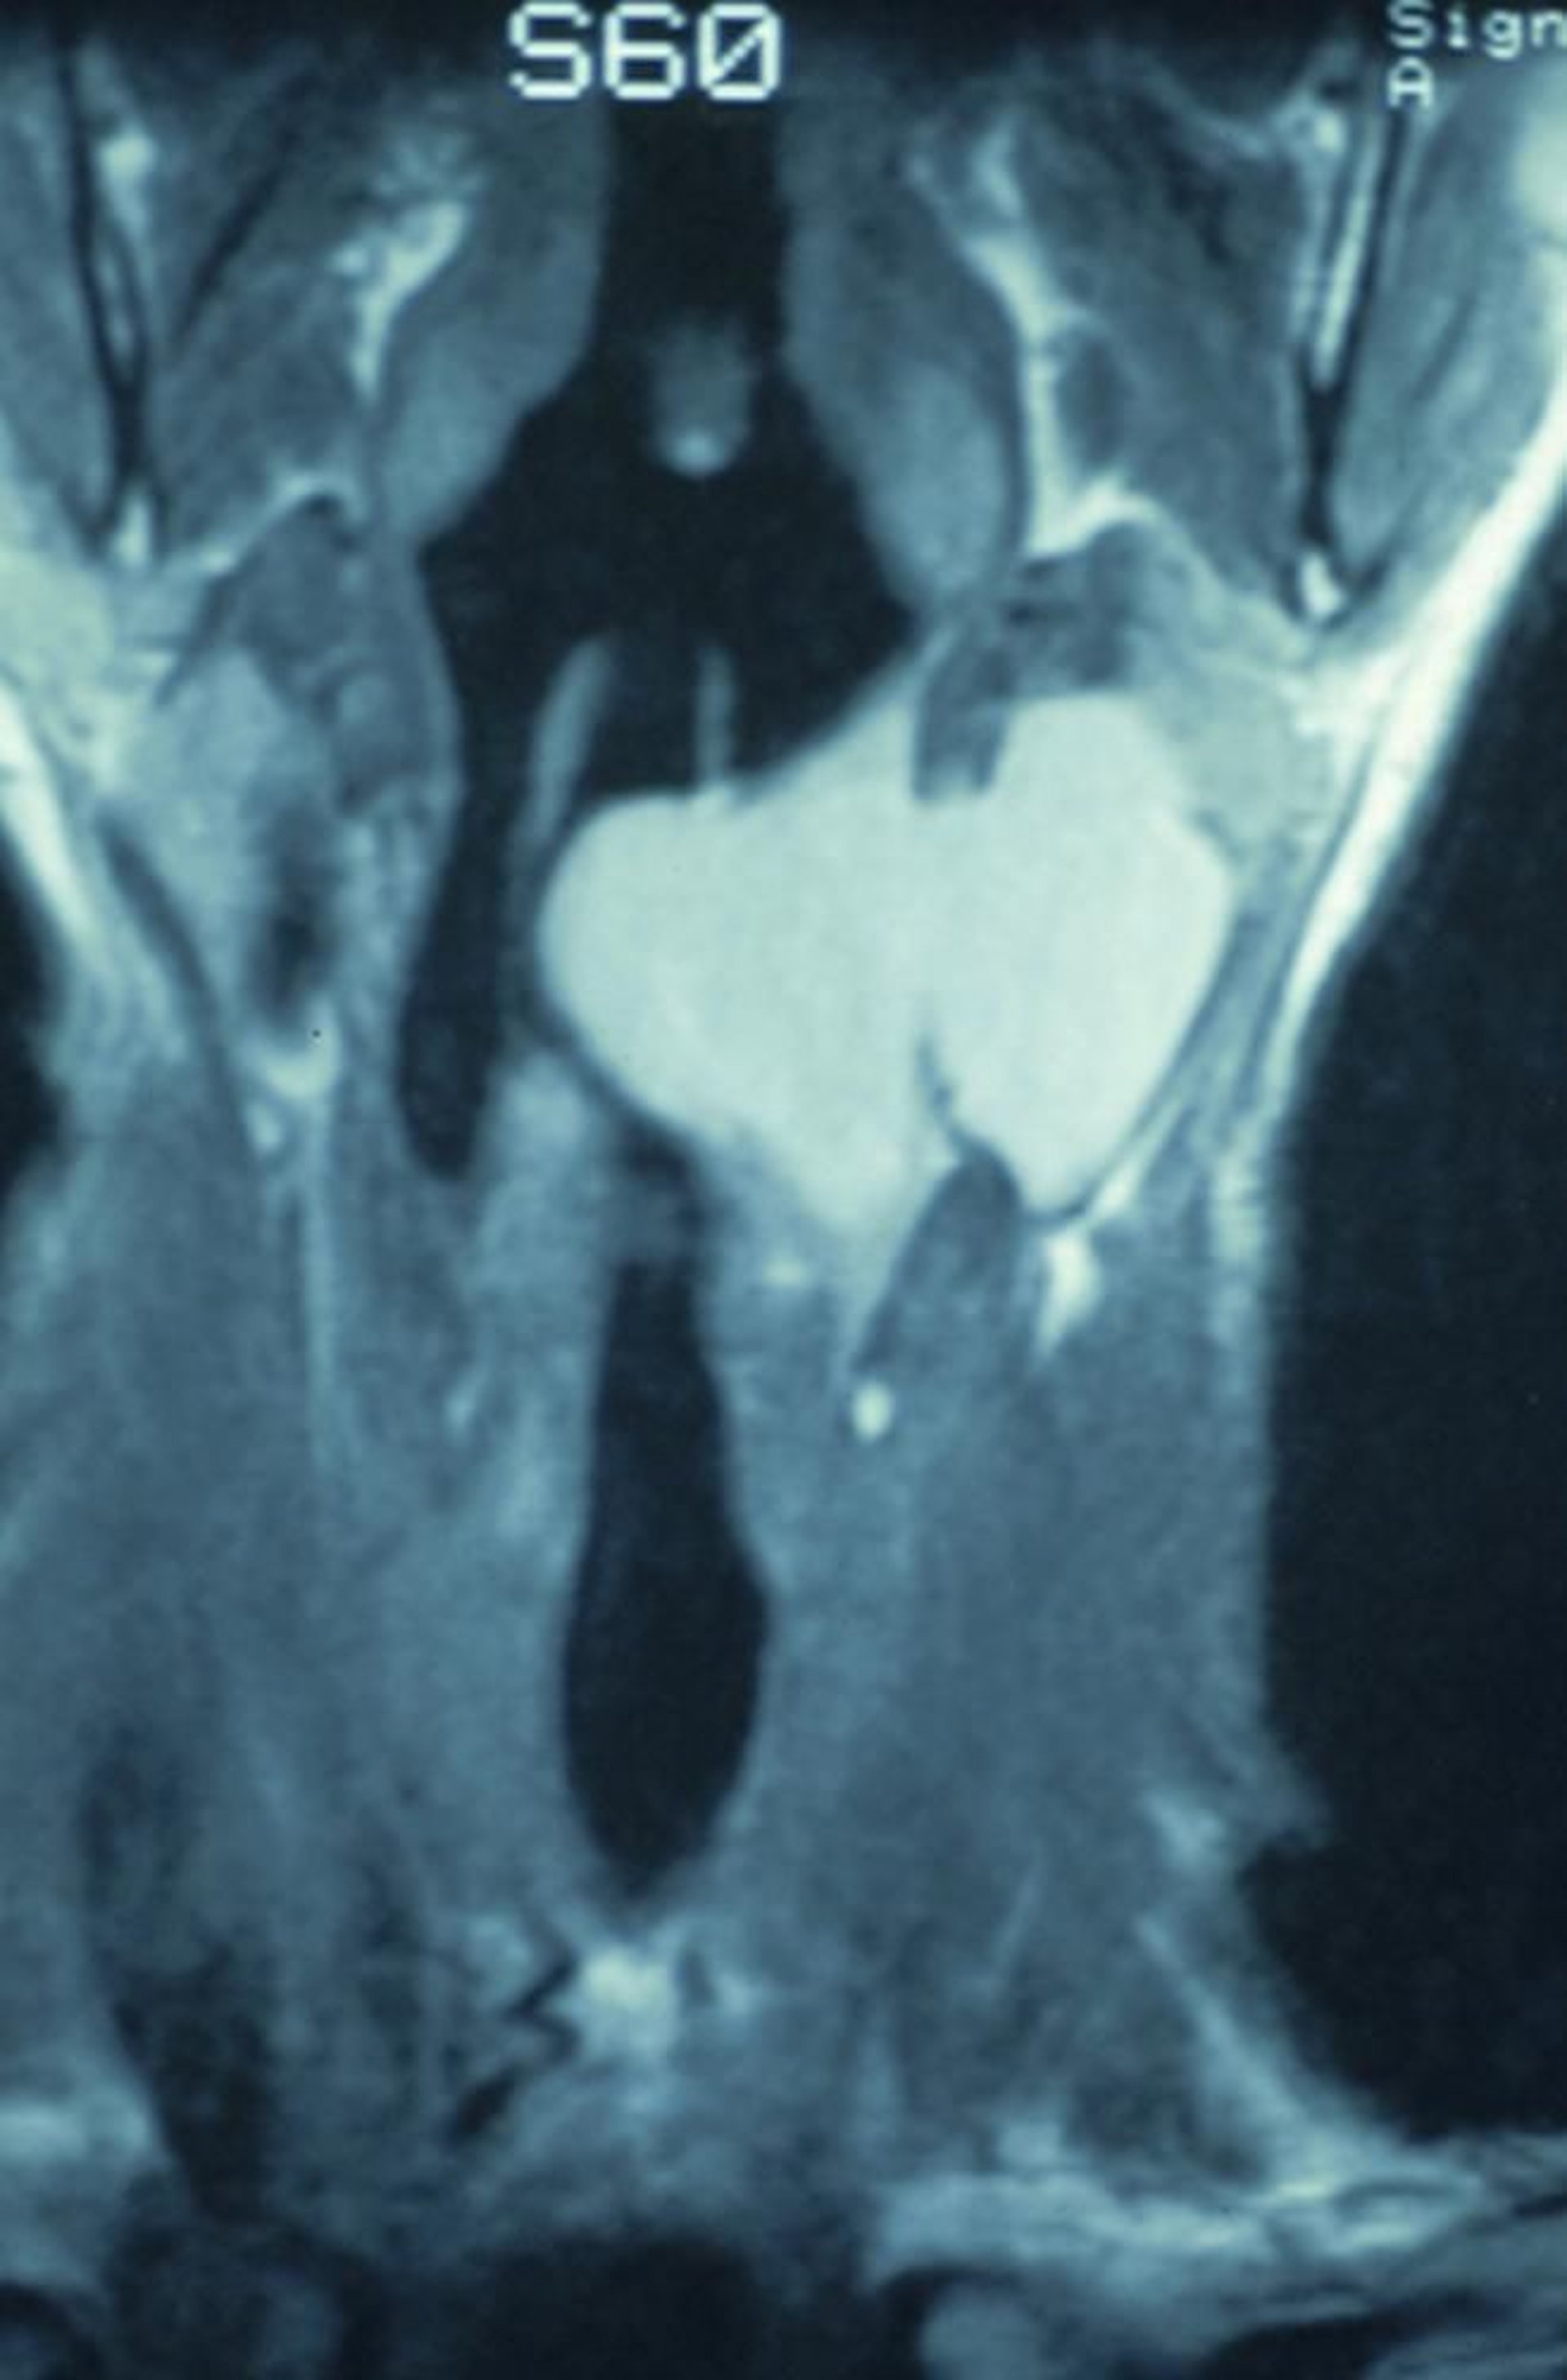

Laryngocèle mixte

Cette IRM coronale montre une laryngocèle combinée qui commence à l'intérieur du larynx et s'étend à travers la membrane thyrohyoïdienne, provoquant la formation d'une masse dans le cou.

Image provided by Clarence T. Sasaki, MD.